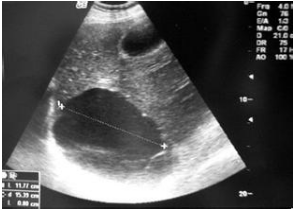

一、肝囊腫

肝囊腫,通俗地說,就是肝內(nèi)有類圓形的囊腔,內(nèi)含體液。根據(jù)數(shù)量,可分為單發(fā)和多發(fā)。肝囊腫是一個完全良性的疾病,絕不會惡變。一般人查體發(fā)現(xiàn)的肝囊腫都不需要處理,只有囊腫特別大,壓迫到臨近的胃之類的臟器,引起吃飯后飽脹等不適,才需要處理。而即使處理,也是微創(chuàng)手術(shù),所以不論什么情況,都不用太過擔心。